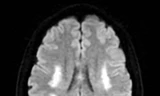

Nhờ xác định rõ thời điểm khởi phát triệu chứng, bệnh nhân được đưa đến bệnh viện cấp cứu trong “thời gian vàng”. Sau khi thăm khám và chẩn đoán hình ảnh, các bác sĩ xác định bệnh nhân bị đột quỵ nhồi máu não và chỉ định điều trị tiêu sợi huyết. Sau khi được tiêm thuốc, các triệu chứng thần kinh của người bệnh dần phục hồi, sức khỏe bình phục tốt.